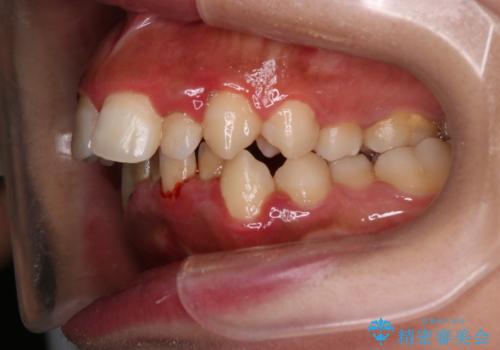

前歯の出っ張りとガタつきを改善

- 「前歯が出ていて並びも悪いのが気になる」との主訴で来院されました。診察の結果、上顎前歯の前突と中等度の叢生(ガタつき)が認められ、歯がきれいに並ぶスペースが不足していました。横顔のバランスと歯並びの両方を整えるため、上顎の左右の第一小臼歯2本を抜歯し、前歯を内側に下げながら歯列全体を整える治療計画を立てました。

治療はインビザラインによって進め、抜歯スペースを使って前歯を内側に引き込みながら、歯のガタつきも順に整えていきました。初期の段階で前歯の見た目が大きく変わり、患者さんにも「印象が柔らかくなった」と非常に喜んでいただけました。

しかし、途中で来院が途絶えてしまい、インビザラインのアカウント(治療管理期間)が終了。再発注やリカバリーが難しくなったため、治療再開のためにワイヤー矯正の提案を行いましたが、患者さんのご希望により再治療は見送られることとなりました。